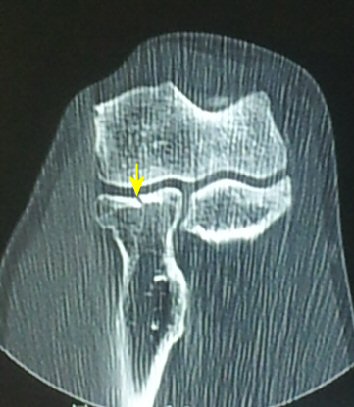

ÀÚ±â°ø¸í°Ë»ç

°ËÇ»ÅÍ ÃÔ¿µ : ¿ä°ñ µÎ ÀåÃà¸é °ñÀý( ±×¸² 6. 7)